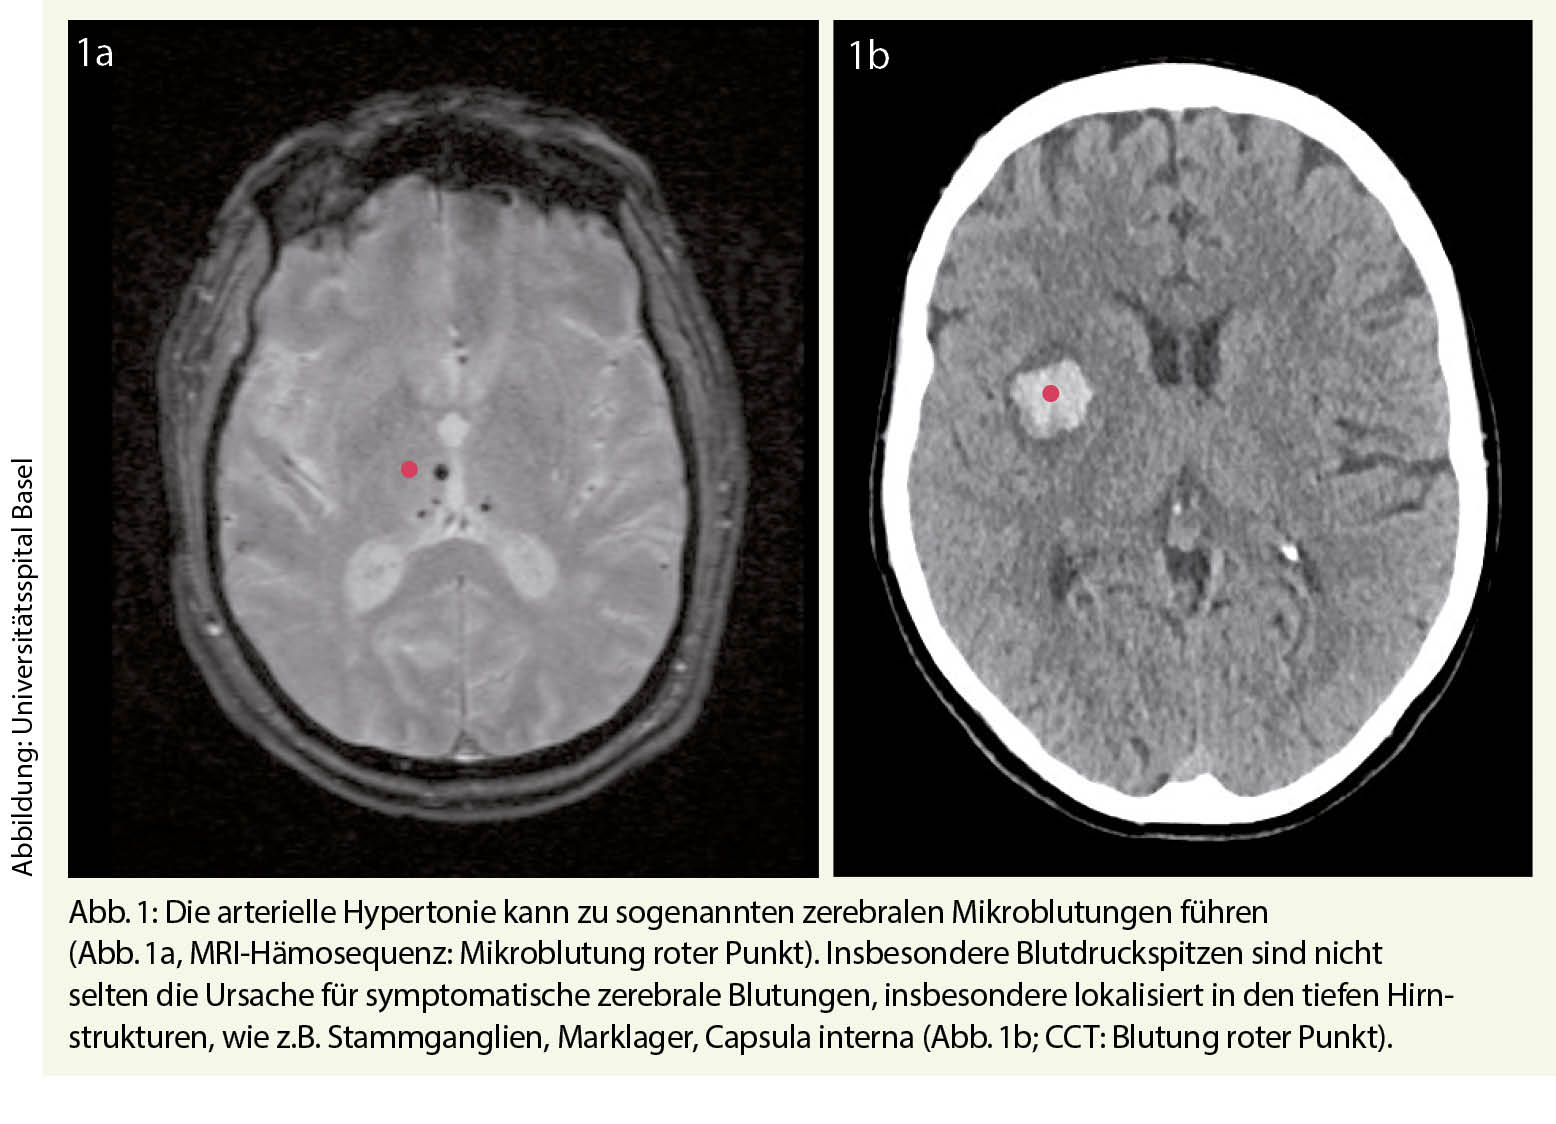

Der endoanale Ultraschall kann bei nachgewiesener Sphinkterinsuffizienz allfällig zugrunde liegende Sphinkterdefekte nachweisen. Abbildung 1 zeigt einen Normalbefund mit zirkulärem echoarmem Internusring. In der Abbildung 2 kann auf der anterioren Hemizirkumferenz (9-3 Uhr) der Internus nach obstetrischen Verletzungen nicht mehr abgegrenzt werden.